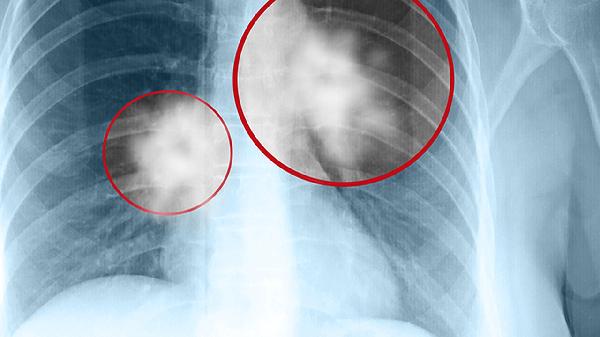

原发性肺癌或转移瘤早期可能表现为孤立性实性结节。恶性结节常呈分叶状、毛刺征等影像特征,可能伴随痰中带血、消瘦等症状。确诊需通过支气管镜或CT引导下穿刺活检,治疗根据病理类型选择手术切除、放疗或靶向药物如吉非替尼片、奥希替尼片等。